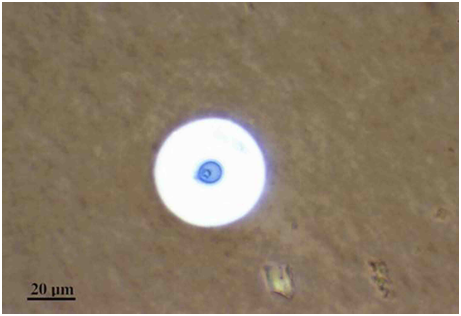

MRI scan was later performed with the suspicion of involvement of brain which highlighted multiple ring enhancing lesions depicting solid cryptococcoma in the brain parenchyma (Figure 3). Microbiological culture on Sabouraud’s dextrose agar showed dark cream coloured smooth moist mucoid colonies positive for Cryptococcus (Figure 4). India ink staining also highlighted the budding yeast cells of C. neoformans surrounded by a characteristic wide gelatinous capsule (Figure 5). All the above investigations confirmed the diagnosis of cryptococcal meningitis. The patient was given intravenous amphotericin B (0.8mg/kg/day) and 5-fluorocytosine (1mg/kg/day) for 8weeks. After 6months of follow up, the fracture healed well with partial resolution of the lytic lesion and no signs of disease progression.

Figure 5 India ink preparation shows budding yeast cells of C. neoformans surrounded by a characteristic wide gelatinous capsule. The yeasts cell are usually spherical to oval, 5-7μm in diameter and typically refractory.